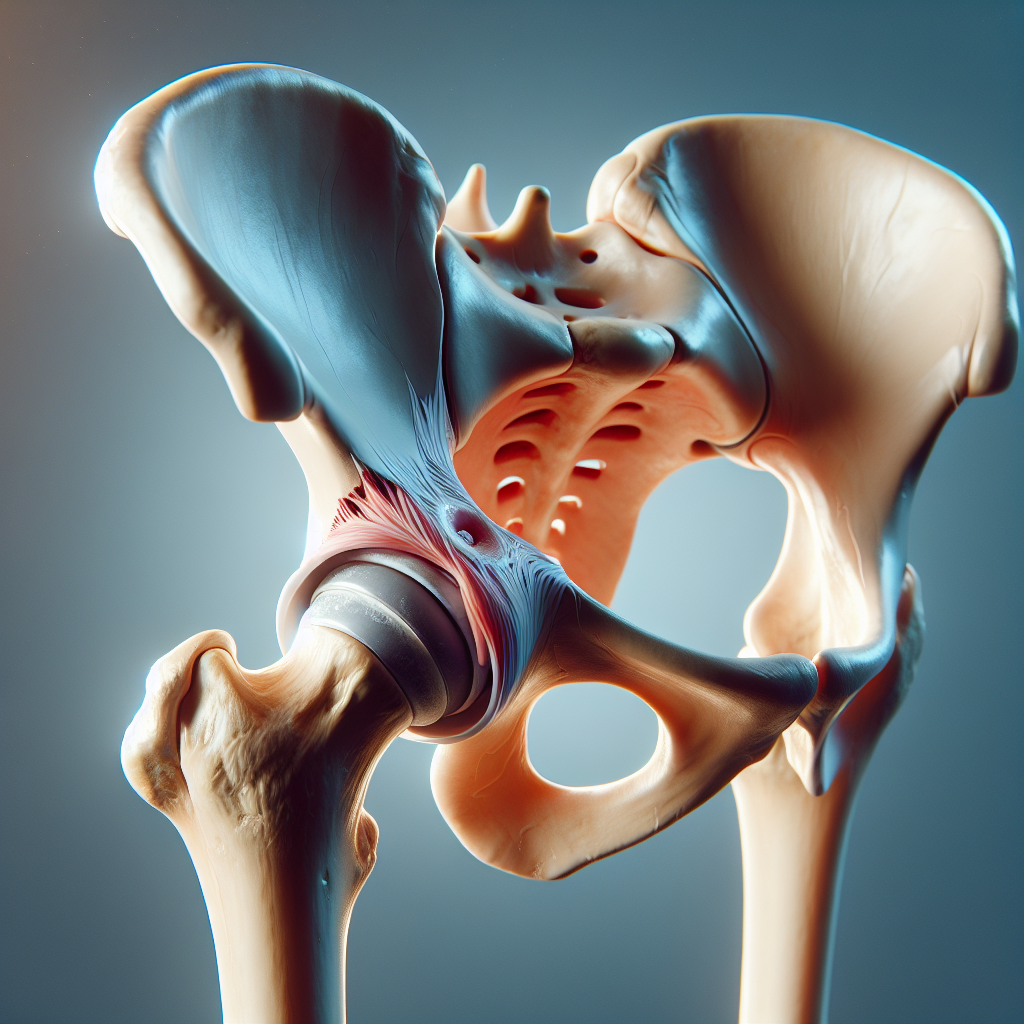

Labral tear basics

A hip labral tear involves the cartilage ring (the labrum) that deepens the hip socket. Tears can cause deep or groin-related hip pain and may be accompanied by a catching, locking, or giving-way sensation during movement. They often arise from a twist or pivot, prior hip joint issues, or structural factors in the joint. Not all labral tears cause noticeable symptoms, and many people benefit from conservative care first. Still, a tear can influence how the joint moves and how it feels during activities like bending, twisting, or crossing your legs.

Bursitis pain most often concentrates on the outer hip, near the greater trochanter, and may feel sharp with activity or a dull, persistent ache with rest. Labral tear pain often centers deeper in the hip or groin and may radiate to the buttock; some people describe a dull ache that worsens with hip rotation or certain positions. Tenderness to palpation over the hip bursa is common with bursitis, while labral tears may be more related to joint movement and timing rather than constant tenderness.

During an evaluation, clinicians look for patterns in how your pain behaves, along with physical signs. A chiropractor in Clark NJ can help coordinate the assessment and explain what each finding might mean. Specific tests focus on hip movement, strength, and the way the joint reacts to certain stresses. Imaging, when indicated, helps confirm the diagnosis: X-rays can rule out arthritis or bone-related changes, while MRI is more sensitive for detecting labral tears. Ultrasound may help assess soft tissues around the bursa in some cases. Red flags—such as severe pain with weight bearing, fever, or numbness that accompanies leg symptoms—require prompt urgent care.

Key physical exam maneuvers

Exam maneuvers might include observing how you rotate your hip, how your leg moves while lying down, and whether certain positions reproduce the pain. A labral tear might be suggested by pain with internal rotation and flexion, while bursitis may show focal tenderness and irritation over the outer hip area without the same joint-specific pain pattern. Your clinician will tailor the exam to your history and daily activities, which helps distinguish mechanical hip pain from other potential sources.

Imaging and when it’s helpful

Imaging can clarify unclear cases. An X-ray helps assess bony structures and rule out arthritis, while MRI provides detailed images of soft tissues, including the labrum, cartilage, and surrounding muscles. If pain is persistent or limiting function, imaging can guide decisions about physical therapy, injections, or other conservative options. A chiropractor in Clark NJ can help interpret imaging results in the context of your symptoms and goals.